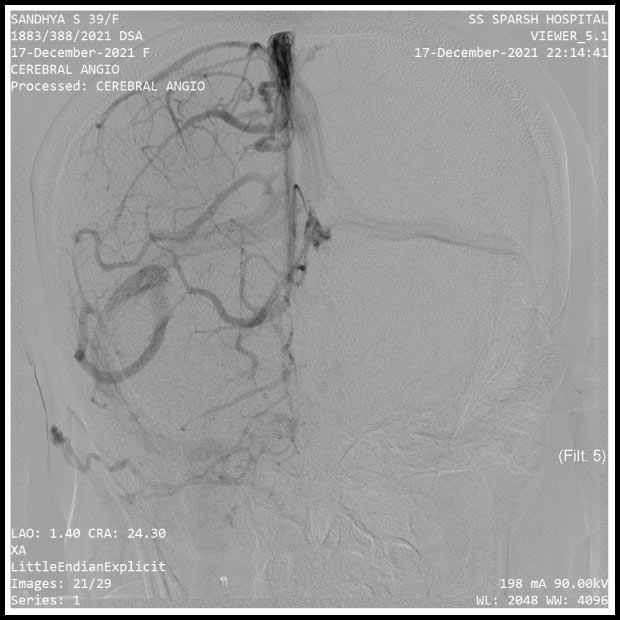

TEST REPORTS FROM THE HOSPITAL

Pics show the test reports from the hospital. The brain aneurysm is clearly noticeable.